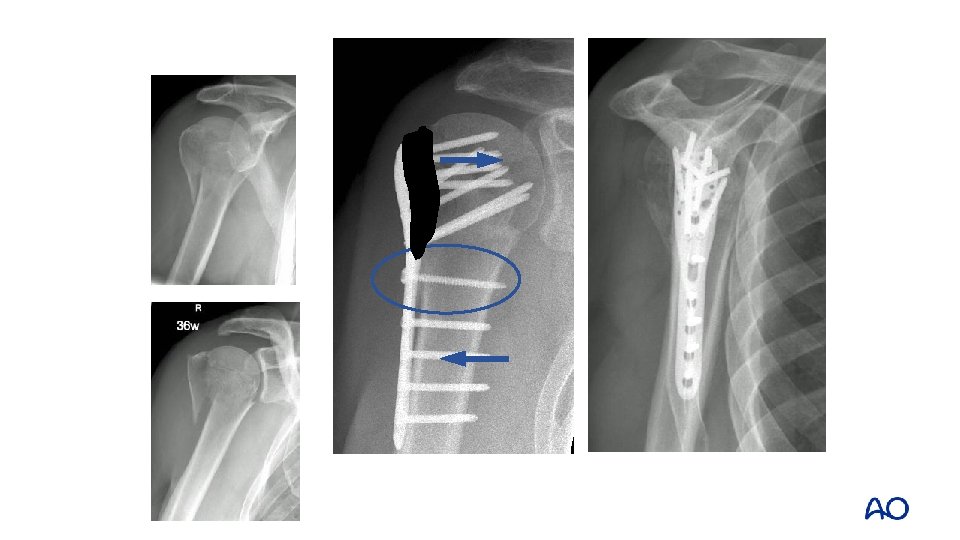

Varus angulated 3 -part lesser tuberosity Trauma Intraoperative 1 year

Proximal humeral fractures—locked plate fixation Complications: • Varus malunion: • Screw penetration: 12– 14% • Loss of reduction: 12% • Cut-out: 16% 11%

Significant risk factors for failure • Age > 63 years • Local bone mineral density < 95 mg/cm 3 • No anatomical reduction • No restoration of the medial cortical support